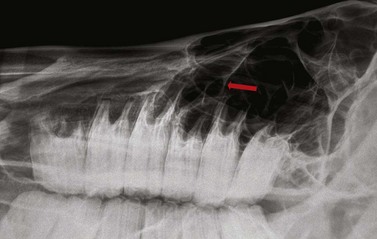

Contrast studies

Placement of a radio-opaque marker over an area of facial swelling and repetition of a radiographic projection (Fig. 13.21) can be an invaluable aid when assessing the clinical significance of radiographic changes. If a cutaneous draining tract is present, as is common in cases of periapical infection of the mandibular cheek teeth or upper 06s and 07s, a blunt metallic probe can be placed into the tract, held in place with tape (Fig. 13.22) and a repeat radiograph taken (Fig. 13.23). This very simple form of contrast study often provides unequivocal evidence that a tooth is infected.

image

Fig. 13.21 Lateral oblique radiograph of the hemimandible of a horse which presented with a swelling on the ventral aspect of its mandible. A radio-opaque marker has been taped to the area of maximal facial swelling, which corresponds to an area of clubbing (short, rounded appearance) of the caudal root of the 08 due to loss of the apex of that root and surrounding radiolucency.

image image

Fig. 13.22 (A & B) A blunt metallic probe placed into a cutaneous discharging tract and secured with radiolucent tape can provide strong evidence as to which tooth is infected in cases of suspected periapical infection.